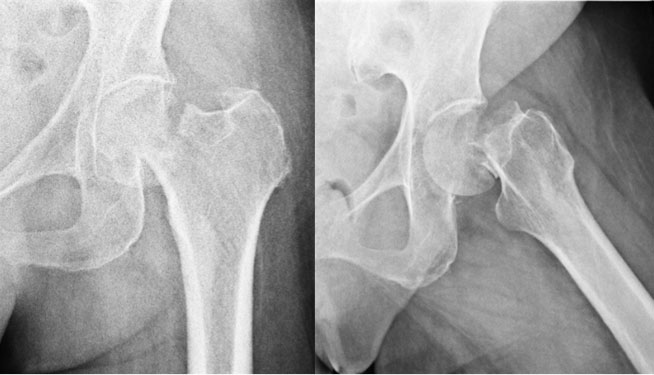

Injury

This 54 year old lady, smoker, had a slip and fell on her hip. There was a fracture of the neck of femur on the left side. The options in such a situation are to either fix the fracture or replace the joint either half (Hemiarthroplasty-only the ball of the joint is replaced) or complete (Total Hip Replacement-boththe ball & socket are replaced).